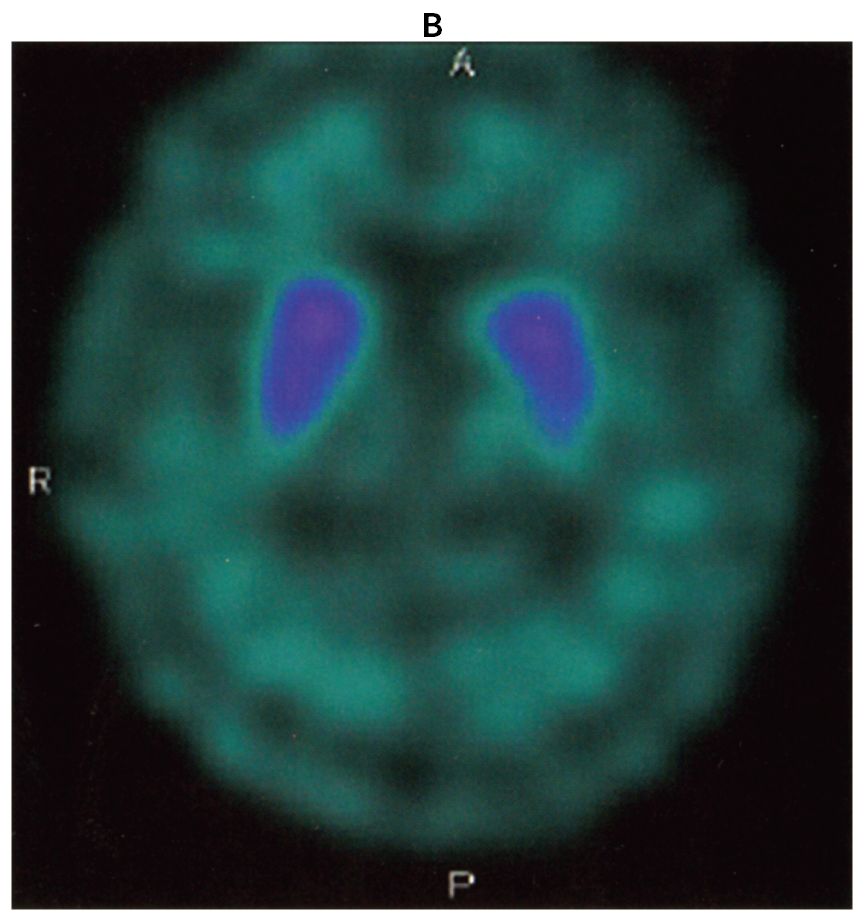

69歳の男性。転びやすいことを主訴に来院した。10年前から糖尿病でインスリン療法を行っている。3年前から歩行時に前のめりになり転倒することが頻回になり,5か月前に左上腕骨を骨折した。診察時,表情は乏しく,やや小声であった。眼球運動は上下方向に制限があり,筋強剛は頸部に強く認めたが四肢では軽かった。四肢の腱反射は正常で,Babinski徴候を認めない。便秘もない。レボドパ〈L-dopa〉の内服による治療効果は認められなかった。頭部単純MRIのT1強調像(A)とドパミントランスポーターSPECT(B)とを下に示す。